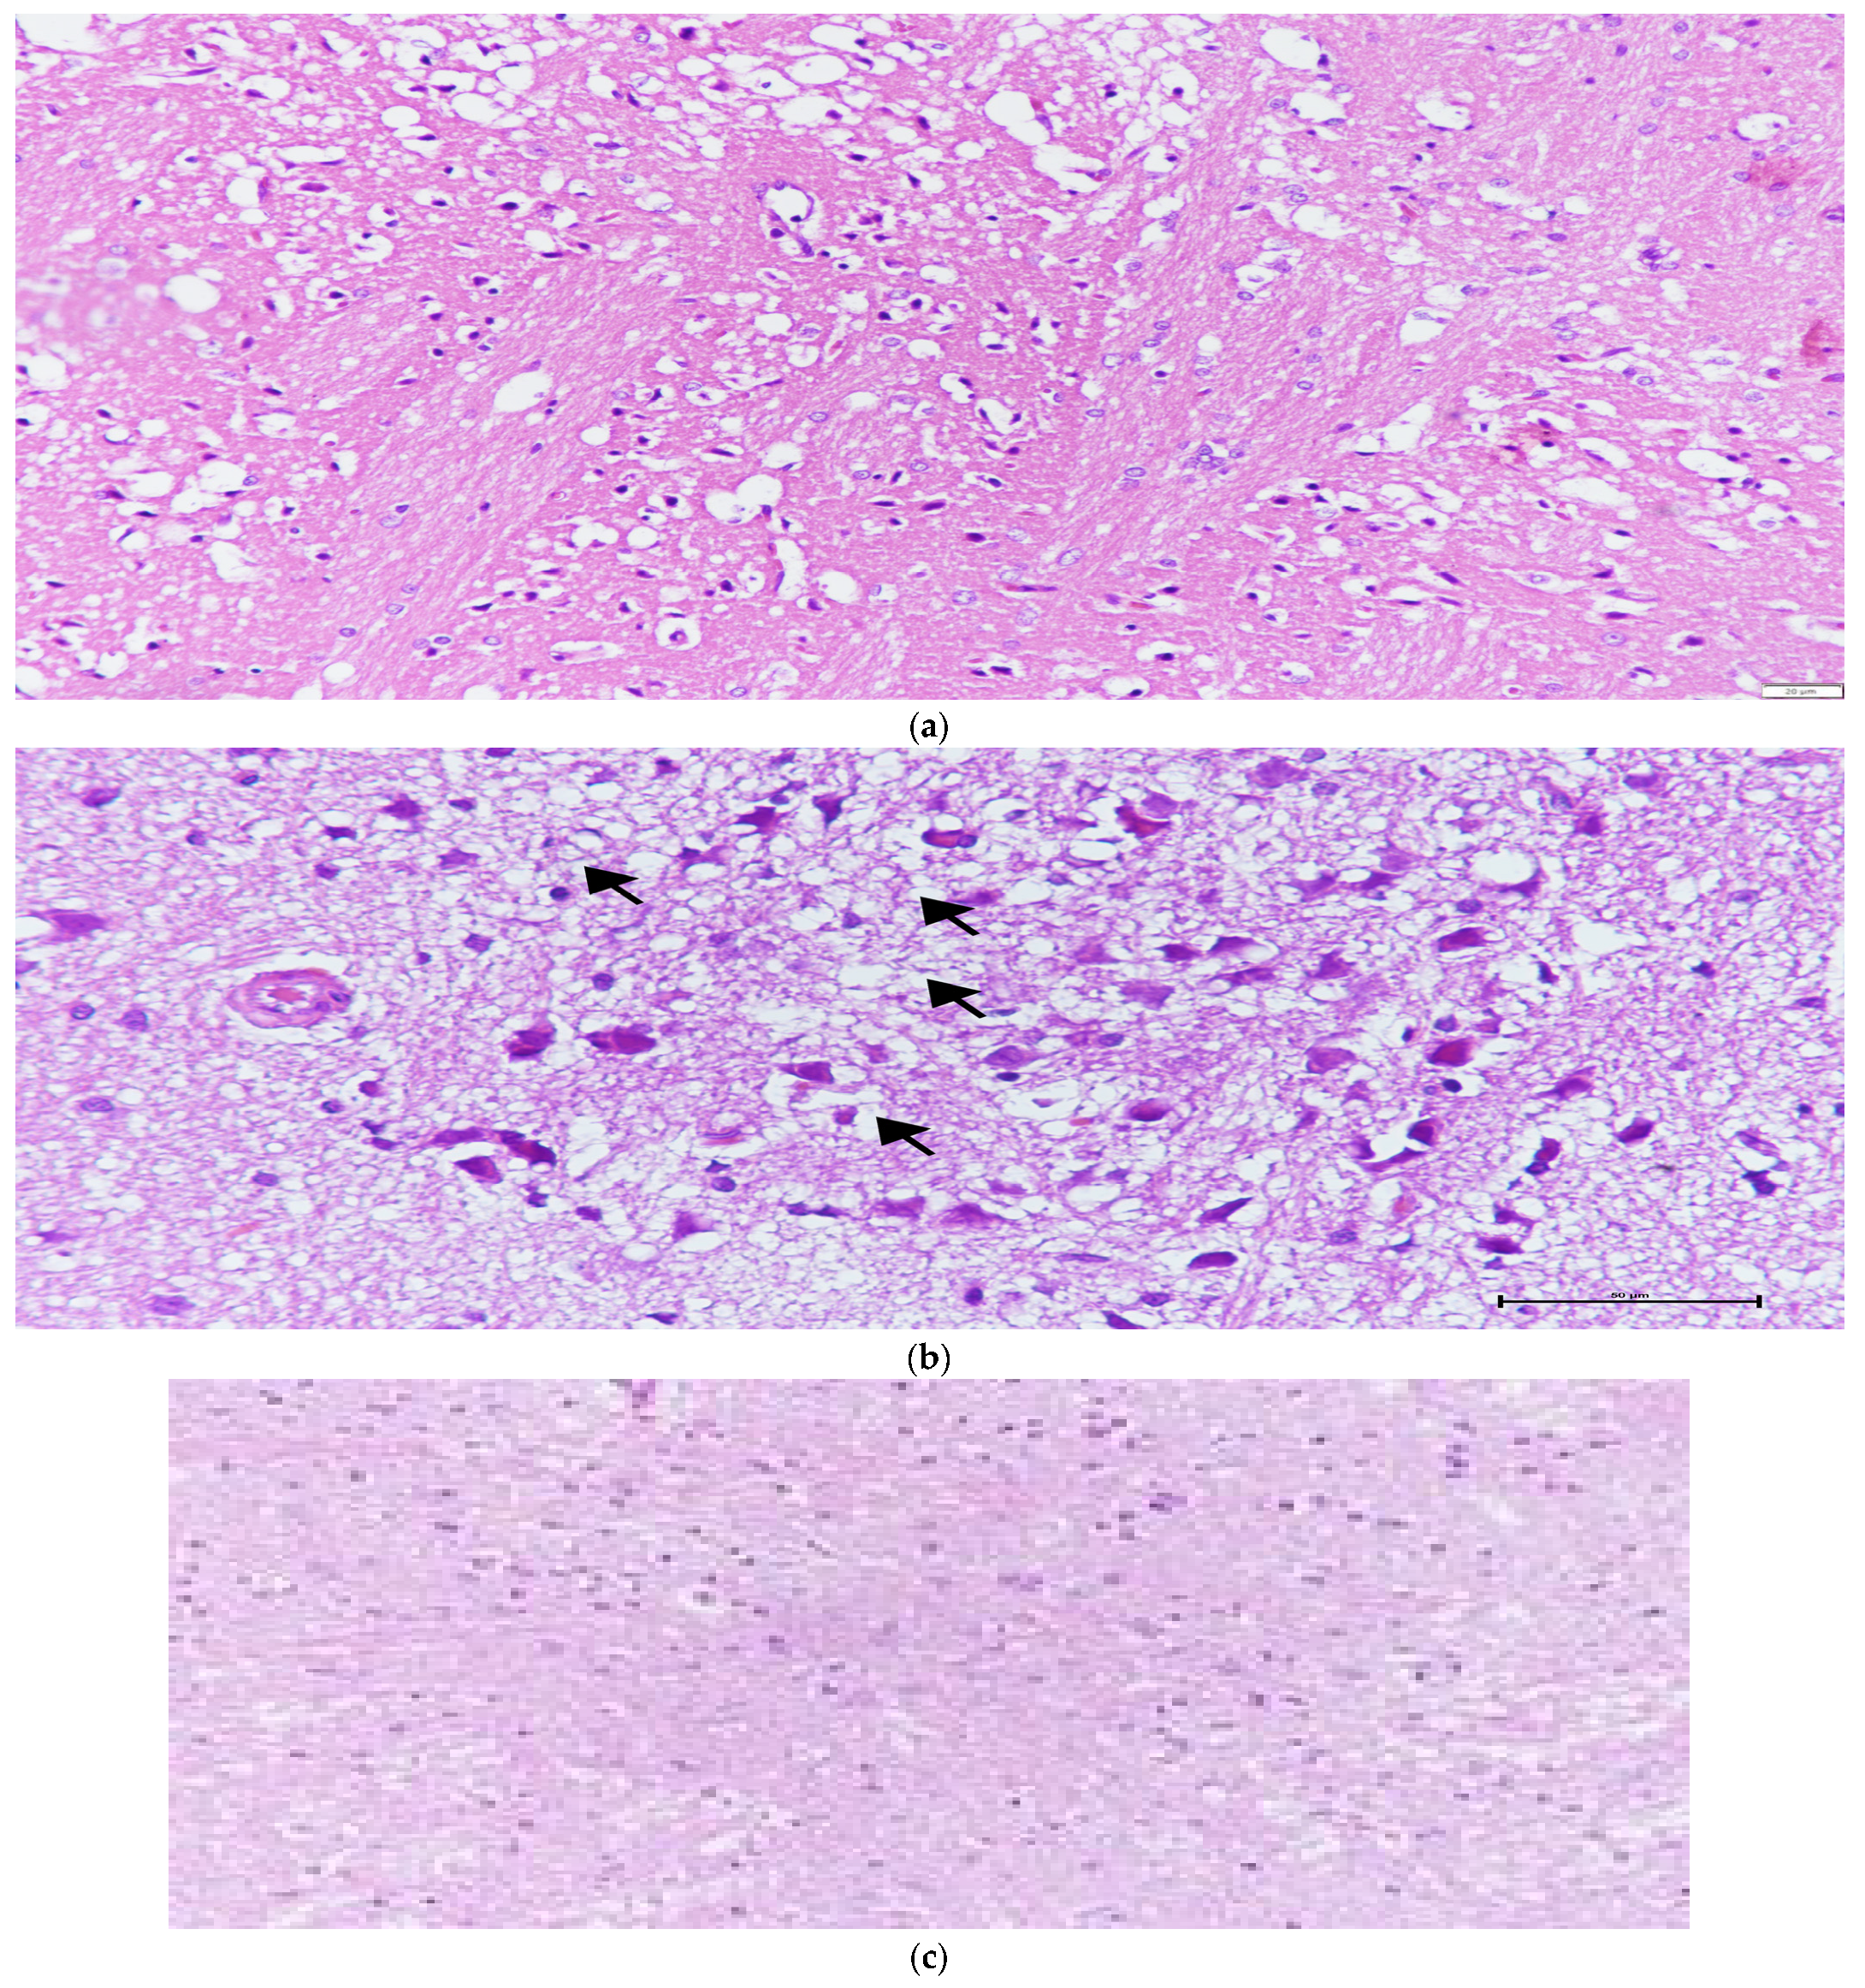

| Cellular Eosinophilic, Pyknotic Degeneration (Mean ± SD) | Vascular Congestion (Mean ± SD) | Vacuolization (Mean ± SD) | Necrosis (Infarct) (Mean ± SD) | Edema (Mean ± SD) | |

|---|---|---|---|---|---|

| Control (n = 8) | 0.75 ± 0.46 | 1.25 ± 0.46 | 0.50 ± 0.54 | 0.00 ± 0.00 | 0.75 ± 0.46 |

| I/R (n = 8) | 2.63 ± 0.52 | 1.88 ± 0.64 | 2.25 ± 0.71 | 2.38 ± 0.74 | 2.13 ± 0.84 |

| Melatonin (n = 8) | 1.63 ± 0.74 | 1.88 ± 0.64 | 1.25 ± 0.71 | 1.38 ± 1.06 | 1.25 ± 0.46 |

| NAC (n = 8) | 2.63 ± 0.502 | 1.88 ± 0.84 | 2.13 ± 0.99 | 2.38 ± 0.92 | 1.88 ± 0.64 |

| Melatonin +NAC (n = 9) | 1.67 ± 0.50 | 1.22 ± 0.44 | 1.33 ± 0.50 | 1.33 ± 0.71 | 1.11 ± 0.33 |